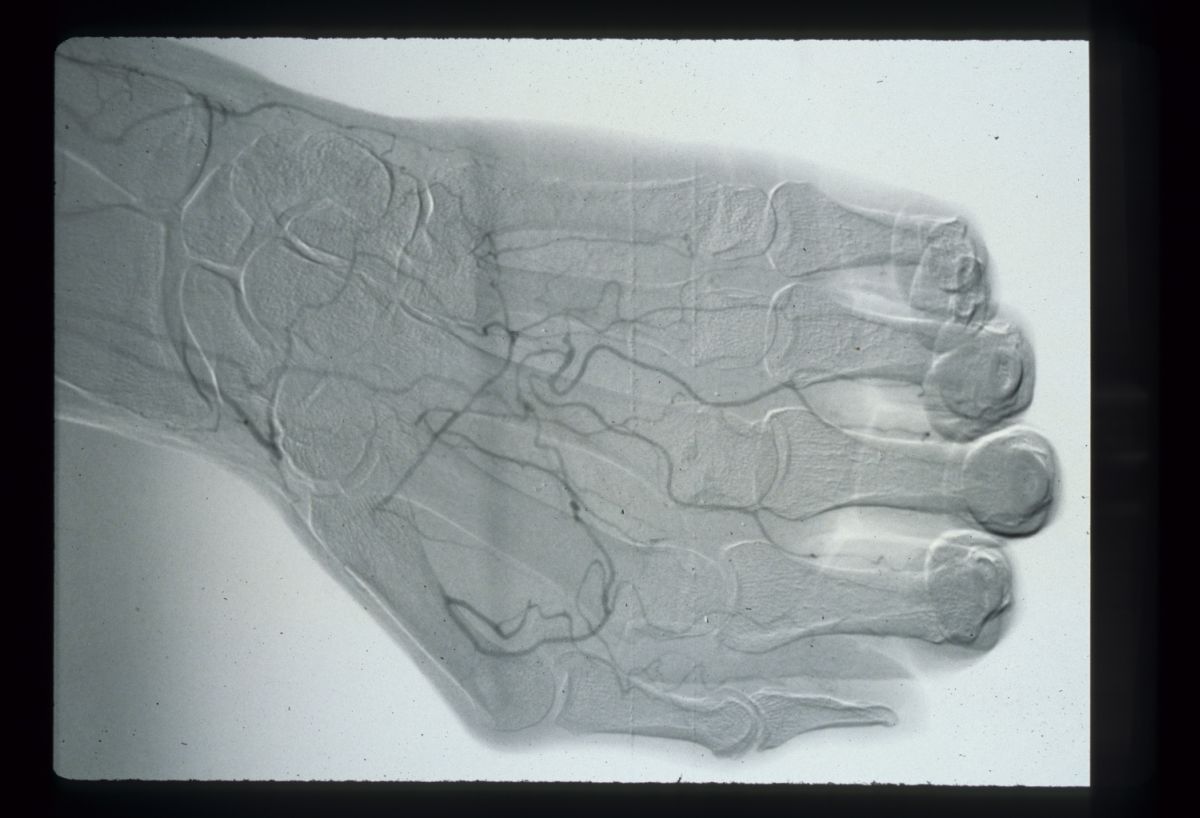

| Case 3. This patient with

nonreconstrutible vascular disease of both hands presented with

multiple ischemic fingertips was managed with local care until

demarcation was complete, allowing uncomplicated amputations with

uneventful healing. |

| Final result, three months

after presentation. |